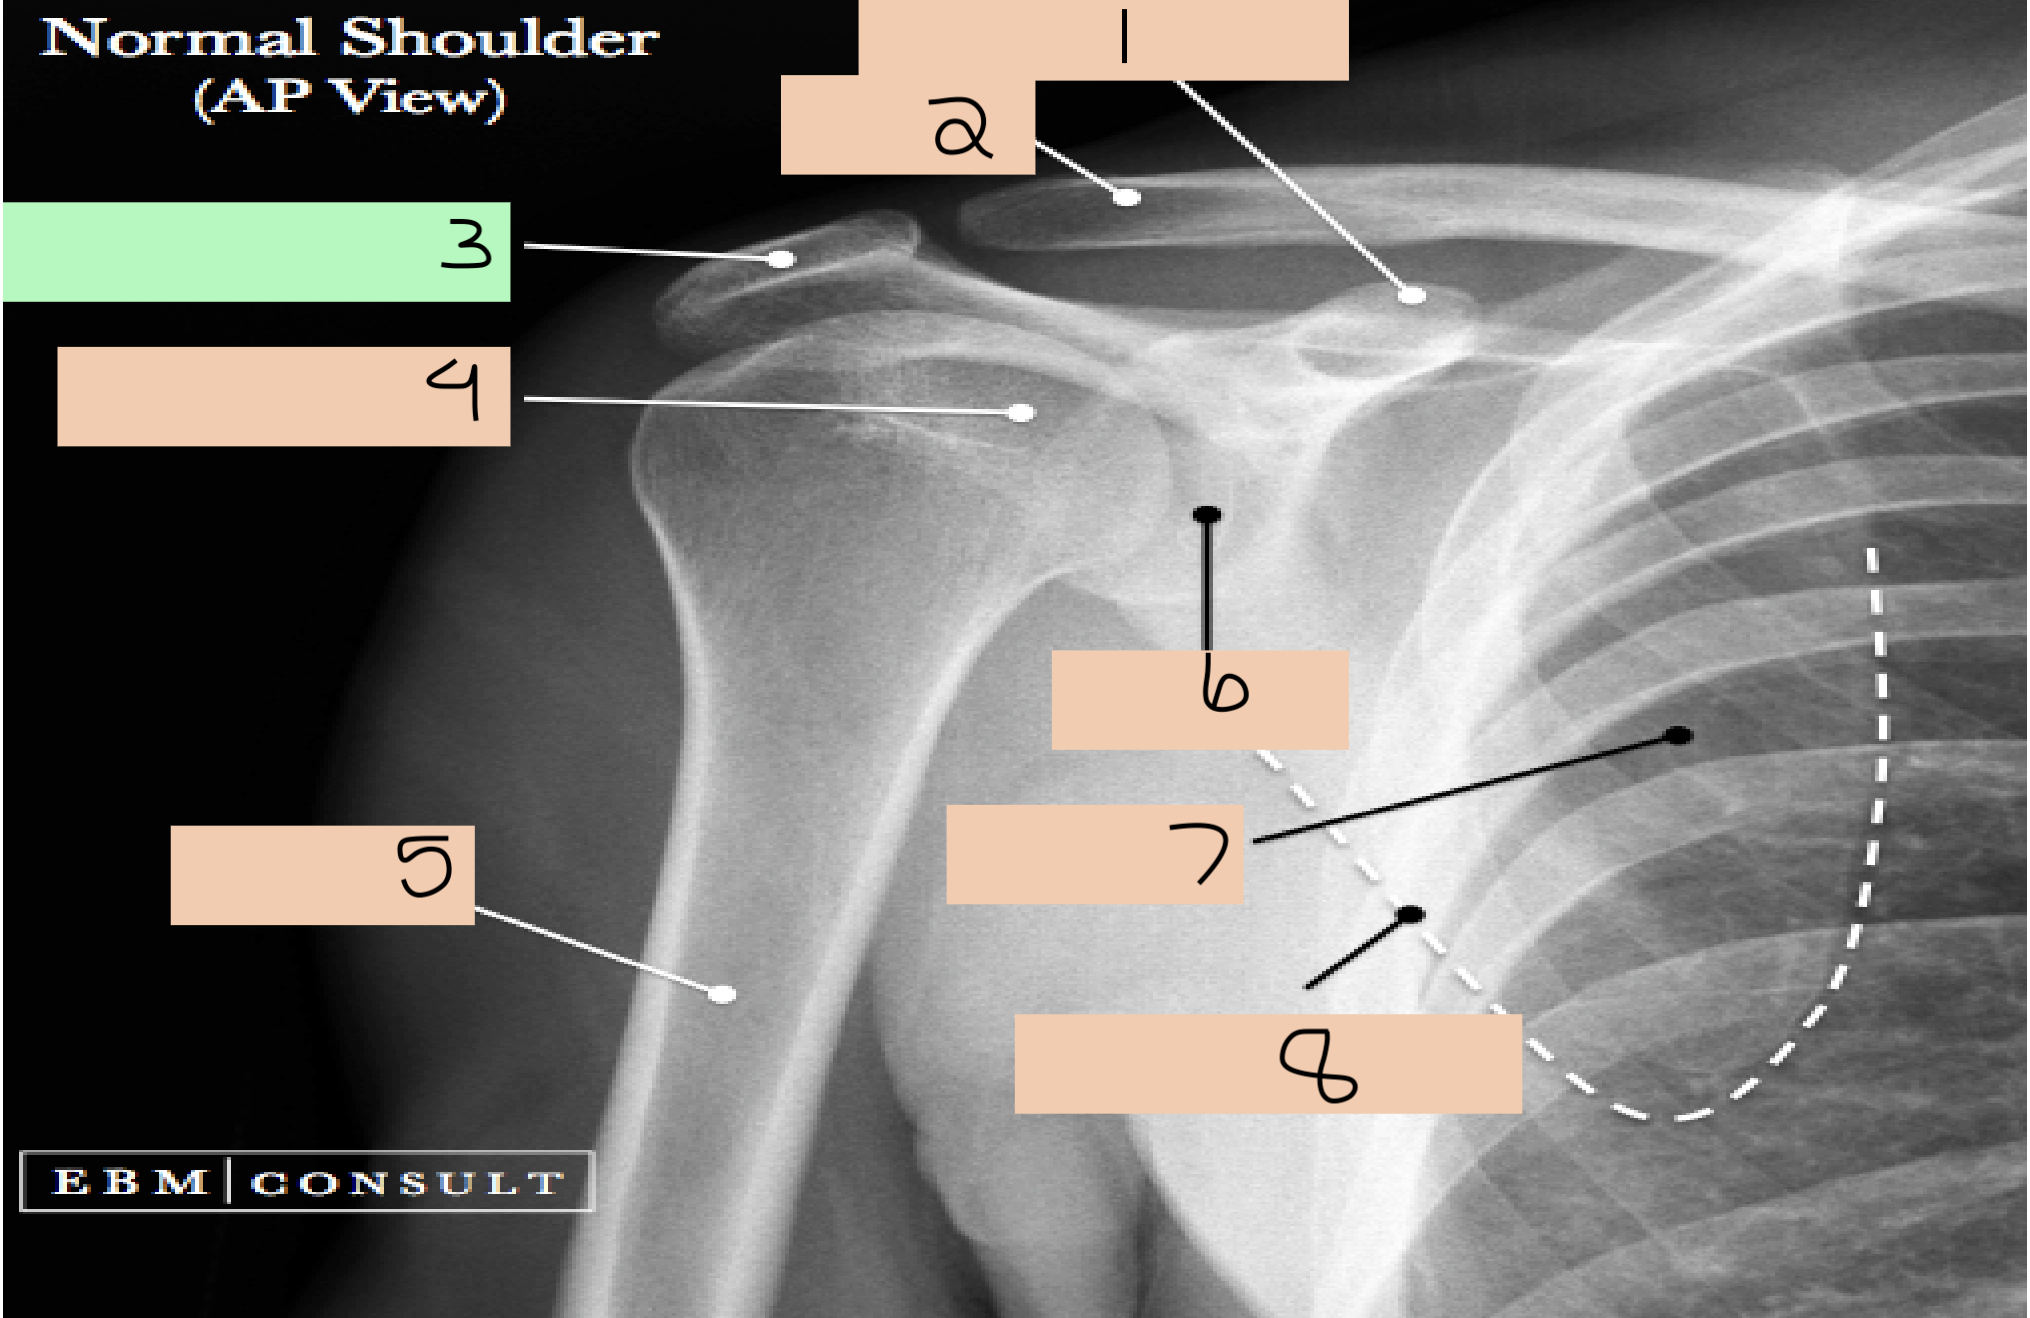

1

acromium process

2

head humerus

3

greater tuberosity

4

surgical neck

5

lesser tuberosity

6

supraglenoid tubercle

7

coracoid process

8

glenoid cavity

9

anatomical neck

10

infraglenoid tubercle

11

lateral border scapula

12

medial border scapula

13

inferior angle of scapula

14

scapula

15

clavicle